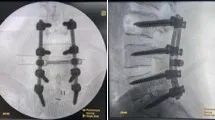

依据最新的循证医学证据,结合科室既往此类手术的成功经验,最终为韩先生制定个性化手术方案。对该患者进行多节段腰椎后路椎弓根螺钉内固定术以重建脊柱稳定性,同时实施椎管内硬脊膜下占位病变切除术以彻底解除神经压迫。

“多节段腰椎内固定术”结合“椎管内占位(肿瘤)切除术”及“神经根减压术”对手术精度要求极高,容不得毫厘之差。在主任龚福太、主任王向阳、主任医师苏小强、主治医师杨涛的默契配合下,手术有序展开,麻醉科团队全程护航。

术中,手术团队克服了患者粘连、精准保护神经、彻底摘除L4椎体上缘水平的椎管内肿瘤、处理L5-S1突出椎间盘并成功置入内固定系统,手术过程顺利。